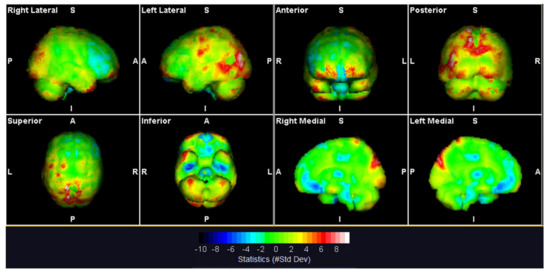

| AAL Region (Left (L) or Right (R)) | SUV Mean | Deviation from Database |

|---|---|---|

| Superior occipital gyrus (L) | 9.2 | 4.9 |

| Cuneus (L) | 10.34 | 4.5 |

| Middle occipital gyrus (L) | 9.33 | 4.5 |

| Cuneus (R) | 10.65 | 4.3 |

| Cerebellum Crus 2 (L) | 8.84 | 4 |

| Superior parietal gyrus (L) | 8.77 | 4 |

| Superior parietal gyrus (R) | 8.32 | 4 |

| Putamen (L) | 8.37 | −4.6 |

| Superior frontal gyrus, medialorbital (R) | 7.41 | −4.6 |

| Fusiform gyrus (R) | 6.75 | −4.9 |

| Putamen (R) | 7.91 | −5.4 |

| Superior frontal gyrus, orbital part (L) | 6.87 | −6 |